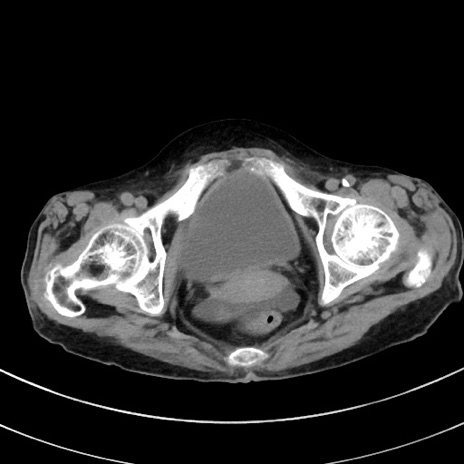

症例33(横断像)

【症例】70歳代 女性

【主訴】心窩部痛

【現病歴】延髄病変の精査・加療にて神経内科入院中。本日より心窩部痛あり。

【既往歴】虫垂炎

【身体所見】右下腹部を中心に圧痛と反跳痛あり。

【データ】WBC 10900、CRP 0.02